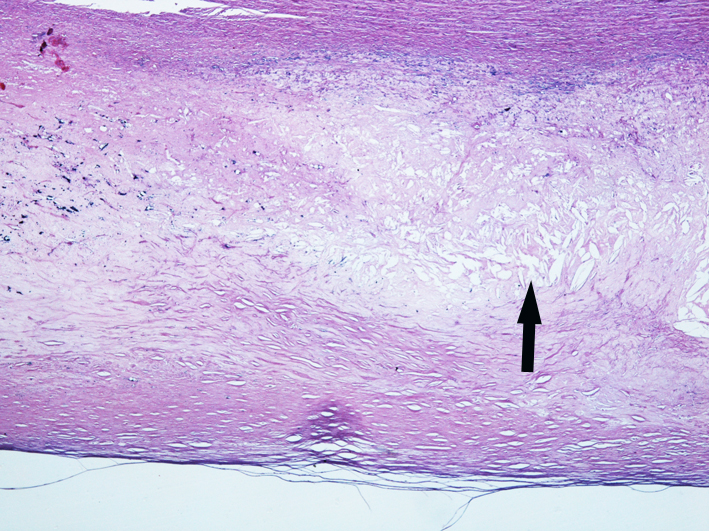

4.主动脉粥样硬化